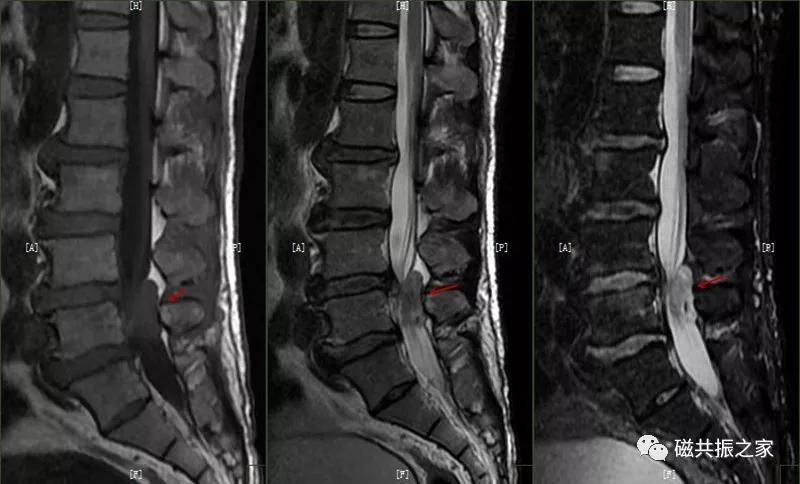

5. 椎间盘变性/突出/膨出/脱出

椎间盘由软骨终板、柔软的髓核(T2WI高信号)和纤维环(T2WI低信号)组成。髓核及纤维环内侧在T2WI呈较高信号,纤维环外侧在T1WI及T2WI呈低信号。

椎间盘变性的常见病理性改变是椎间盘含水量减少(随着年龄的增长,髓核及纤维环内的含水量逐渐减低)、椎间盘的突出,脱出,膨出等改变。椎间盘变性常伴随着纤维环的撕裂和终板变性。

椎间盘变性:椎间盘高度的减低及髓核T2WI信号降低,及髓核与纤维环的分界不清,常伴随椎间盘的突出。

椎间盘突出:当纤维环的完整性受到破坏时,在水平方向的应力作用下,椎间盘向后或侧后突出,对于的硬膜囊、神经根及脊髓受压。

椎间盘脱出:椎间盘突出进一步发展,突出的髓核调入椎管内或与突出部分分离,先后移位形成脱出,甚至髓核可脱离进入椎管内,脱出的髓核在T1WI上呈低、等信号,在T2WI上呈中、高信号,需与椎管占位及滑膜囊肿鉴别。